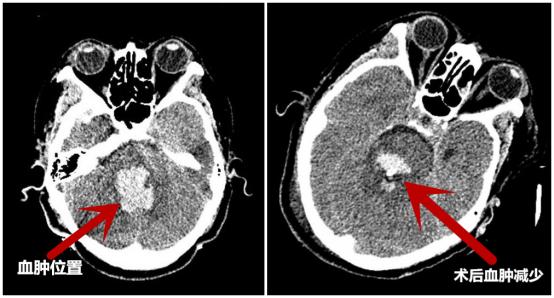

术后复查CT,与术前CT对比血肿明显减少

术后,简国庆院长说道:机器人”辅助定位立体定向脑干血肿穿刺碎吸引流术,与传统手术相比,定位更精确,创伤小;并且通过术前精准的设计穿刺路径,能避开重要神经和血管,使患者能以最小的损伤取得最佳的治疗效果,使患者脑干的大血肿转化为小血肿,同时采用冲洗、药物溶血、引流等方式排空血肿,使患者获得生存机会,后期通过康复促醒提高患者生存质量。

术后15天复查CT

与术前CT对比血肿已基本清除